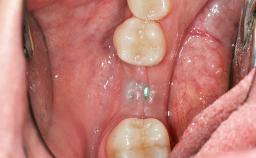

Soft-Tissue Volume Augmentation Using a Connective-Tissue Graft Harvested from the Maxillary Tuberosity

In 1983, a 51-year-old non-smoking patient was referred for the treatment of moderate chronic periodontitis. At the initial examination, 47% of sites exhibited probing depths of 4 to 6 mm. Periodontal therapy consisted of initial periodontal treatment including oral-hygiene instructions and supra- and subgingival debridement, followed by periodontal surgery to eliminate residual pockets.

Soft Tissue Grafting Simultaneous